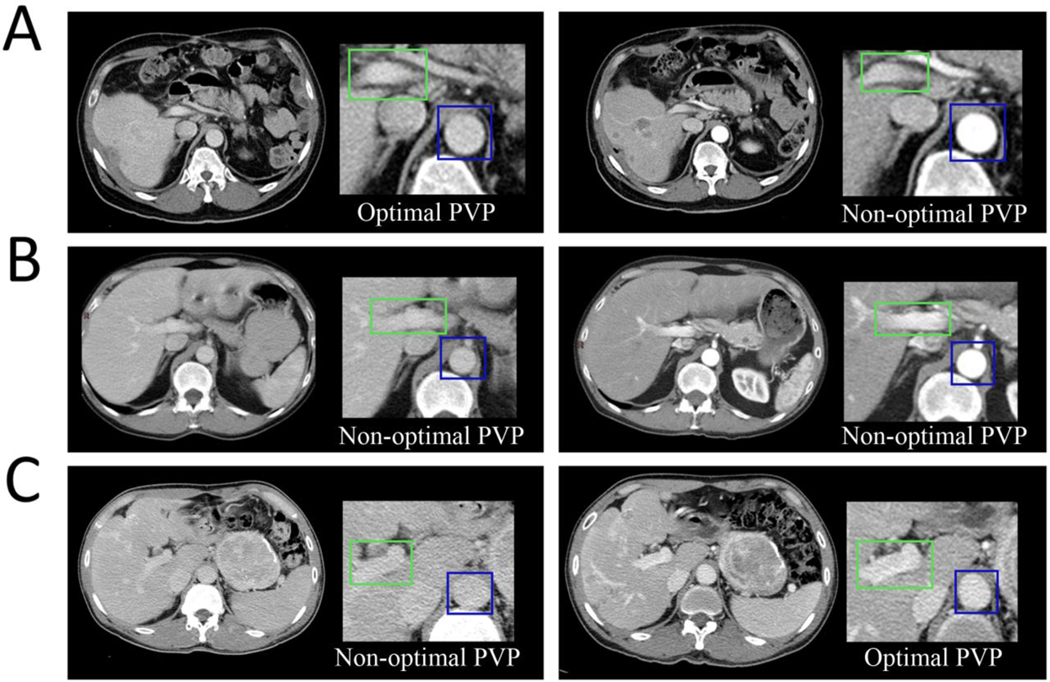

We categorized the PVP timing as optimal or non-optimal. Non-optimal PVP timing included either early or late PVP timing. The definition was based on the relative contrast enhancement within vessels and tissues (24–28). Optimal PVP demonstrated peak enhancement of the liver parenchyma and portal vein, as well as some enhancement of the hepatic veins. Early PVP was defined by contrast still predominantly in the arterial supply as compared with the portal vein. Late PVP was associated with a washout of the hepatic contrast enhancement and approached the nephrogenic phase with more enhancement of the renal medulla. Six examples from three patients are shown in Figure 1.

Fig. 1— Clinical implication of intrapatient variability in Portal Venous Phases timing using CT images acquired at baseline and after treatment initiation.

Optimal PVP timing (A left and C right) was defined by peak enhancement of the liver parenchyma and portal vein, as well as some enhancement of the hepatic veins. Patient A was treated for a NET. At baseline (A, left), the biodistribution of the contrast enhancement product was optimal and significantly differed from the subsequent follow-up (A, right) which was non-optimal as demonstrated by the contrast still being predominantly in the arteries. This might mimic treatment effect if tumor density is used as a response criterion (e.g., Choi, MASS, mRECIST). Patient B was treated for a CRC, at baseline (B, left), the PVP timing was non-optimal because the contrast enhancement in the liver parenchyma and portal vein was low due to the washout of the contrast enhancement. The acquisition after treatment initiation (B, right) was non-optimal as explained by the fact that the contrast agent was still predominantly in the arteries. Patient C was treated for a NET. The PVP timing was non-optimal at baseline(C, left) and optimal during the follow-up (C, right). This will lead to an increase in liver and tumor density at follow-up due to acquisition protocol and might mask treatment effect if tumor density is used as a response criterion.